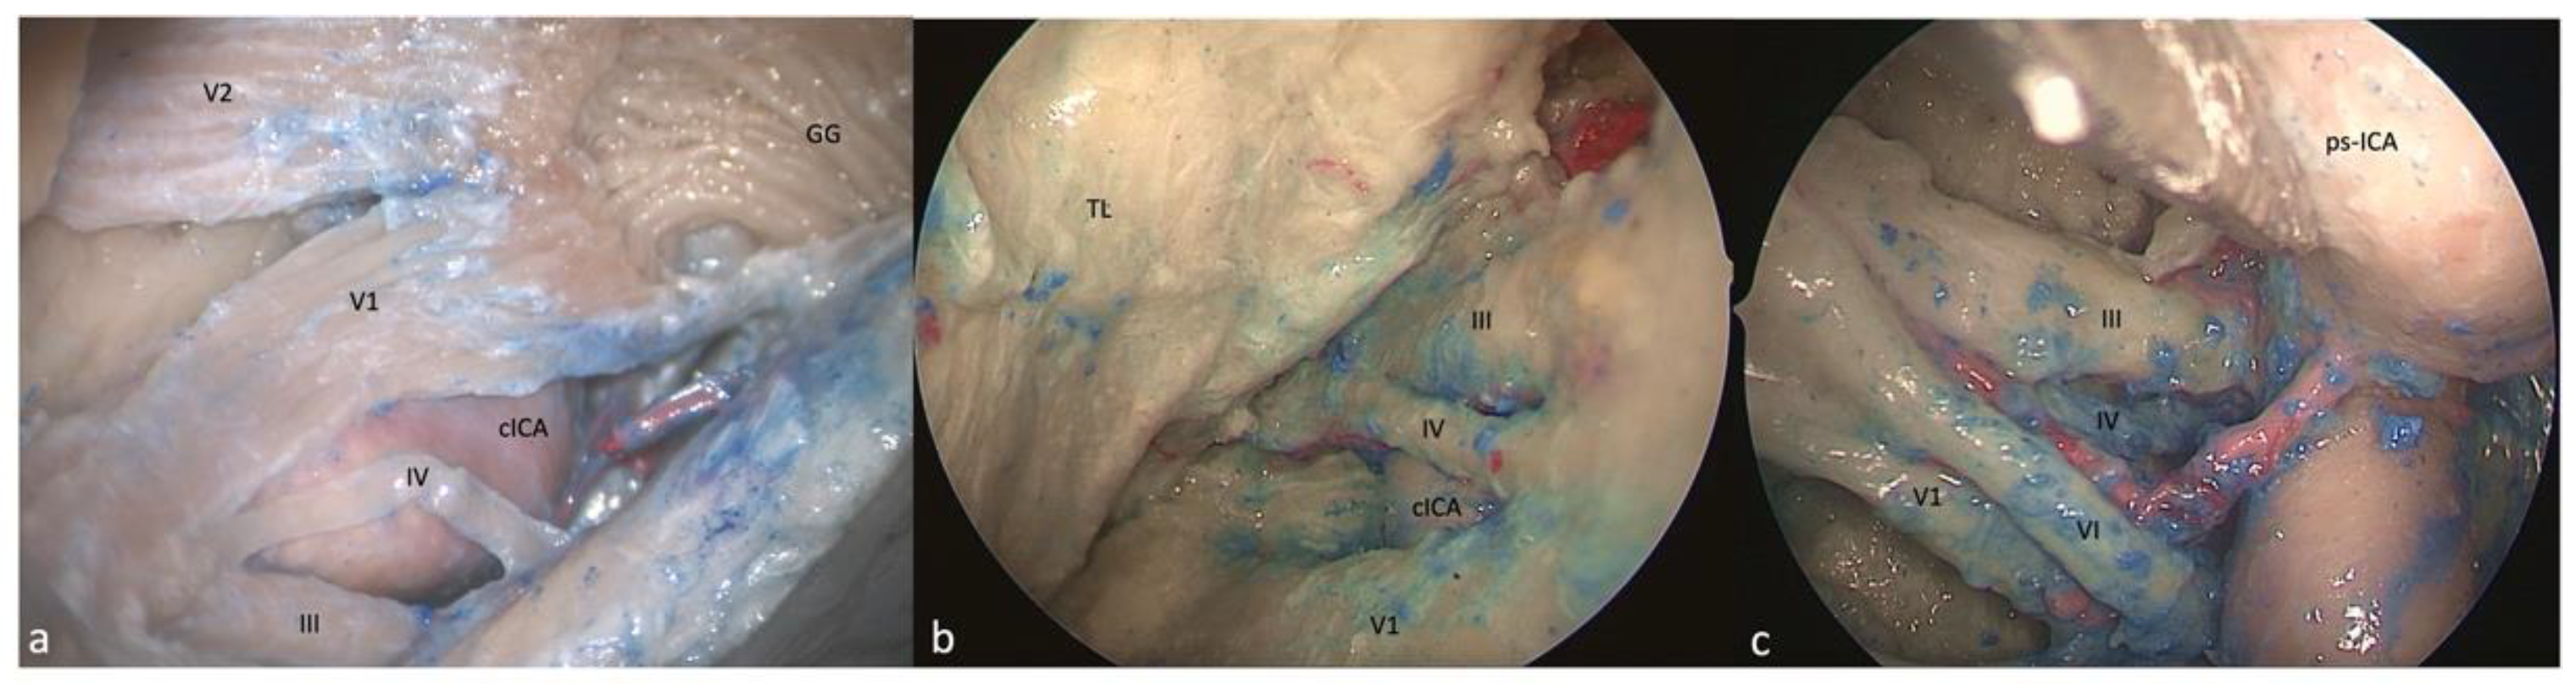

3.1. Clinoid Triangle (Dolenc’s Triangle)

3.1.1. FTOZ Perspective

3.1.2. SETOA Perspective

3.1.3. EEEA Perspective

3.2. Oculomotor Triangle (Hakuba’s Triangle)

3.2.1. FTOZ Perspective

3.2.2. SETOA Perspective

3.2.3. EEEA Perspective